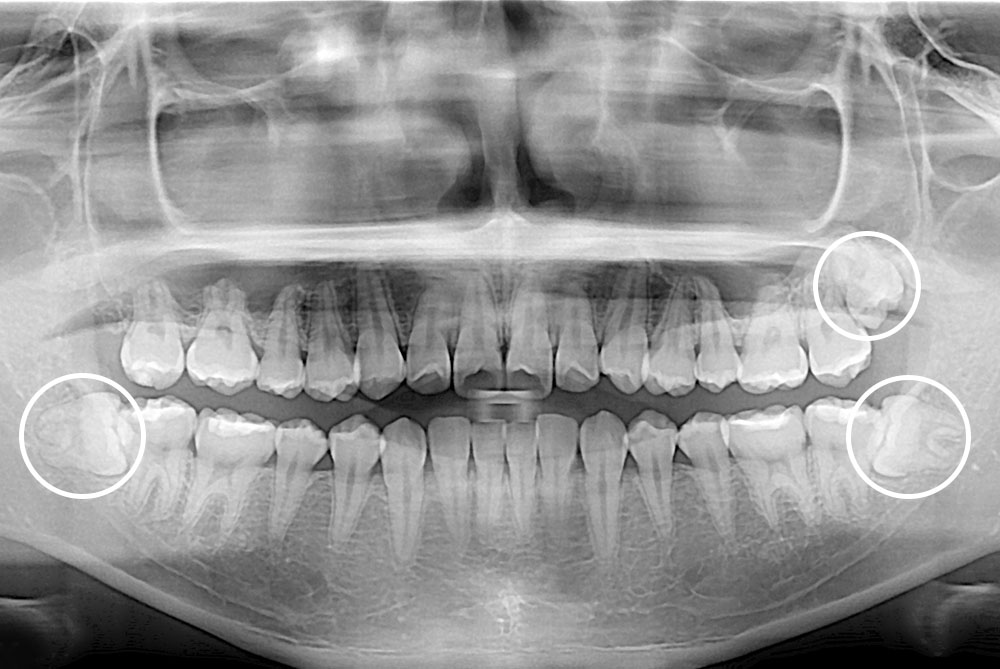

[사랑니] 매복 사랑니 발치

치료전 : 2017-02-14